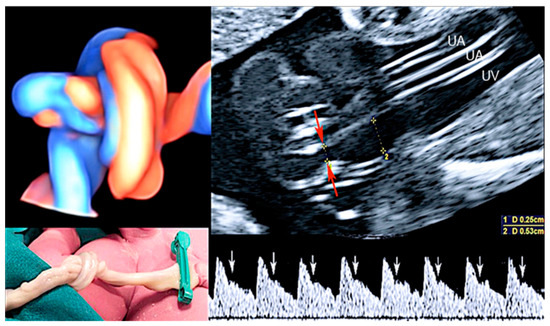

3.1. Cord Coiling

3.2. True Umbilical Cord Knot

3.3. Umbilical Cord Stricture

3.4. Single Umbilical Artery